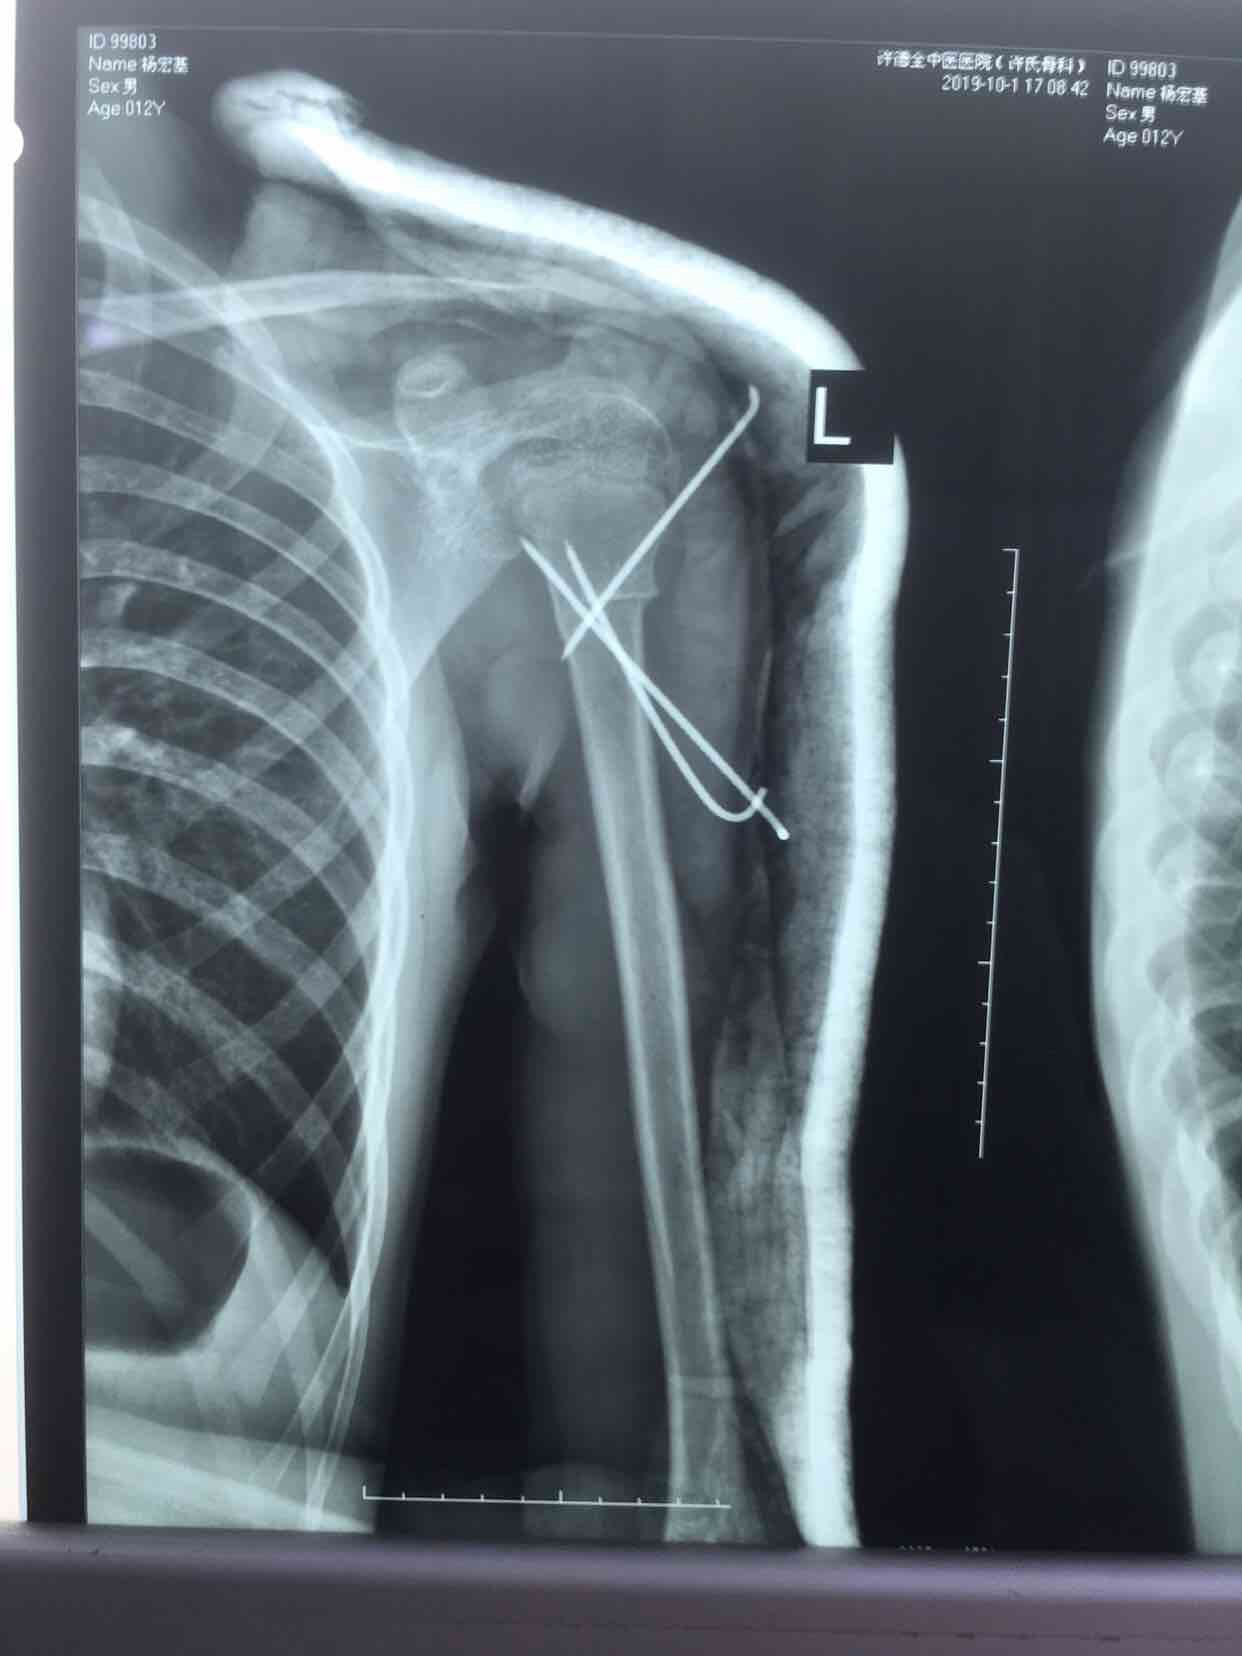

诊断 处理

在臂丛麻醉下行闭合复位内固定术,术后过肩石膏托固定,抗炎,消肿等处理。